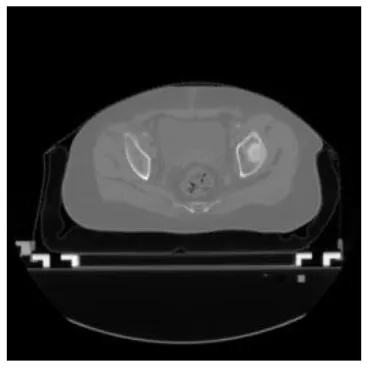

| Input CT image | Organs with manual segmentation | Organ with automatic segmentation | |

| Bladder | ![]() | ![]() | ![]() |

The result of manual and automatic organ segmentation.